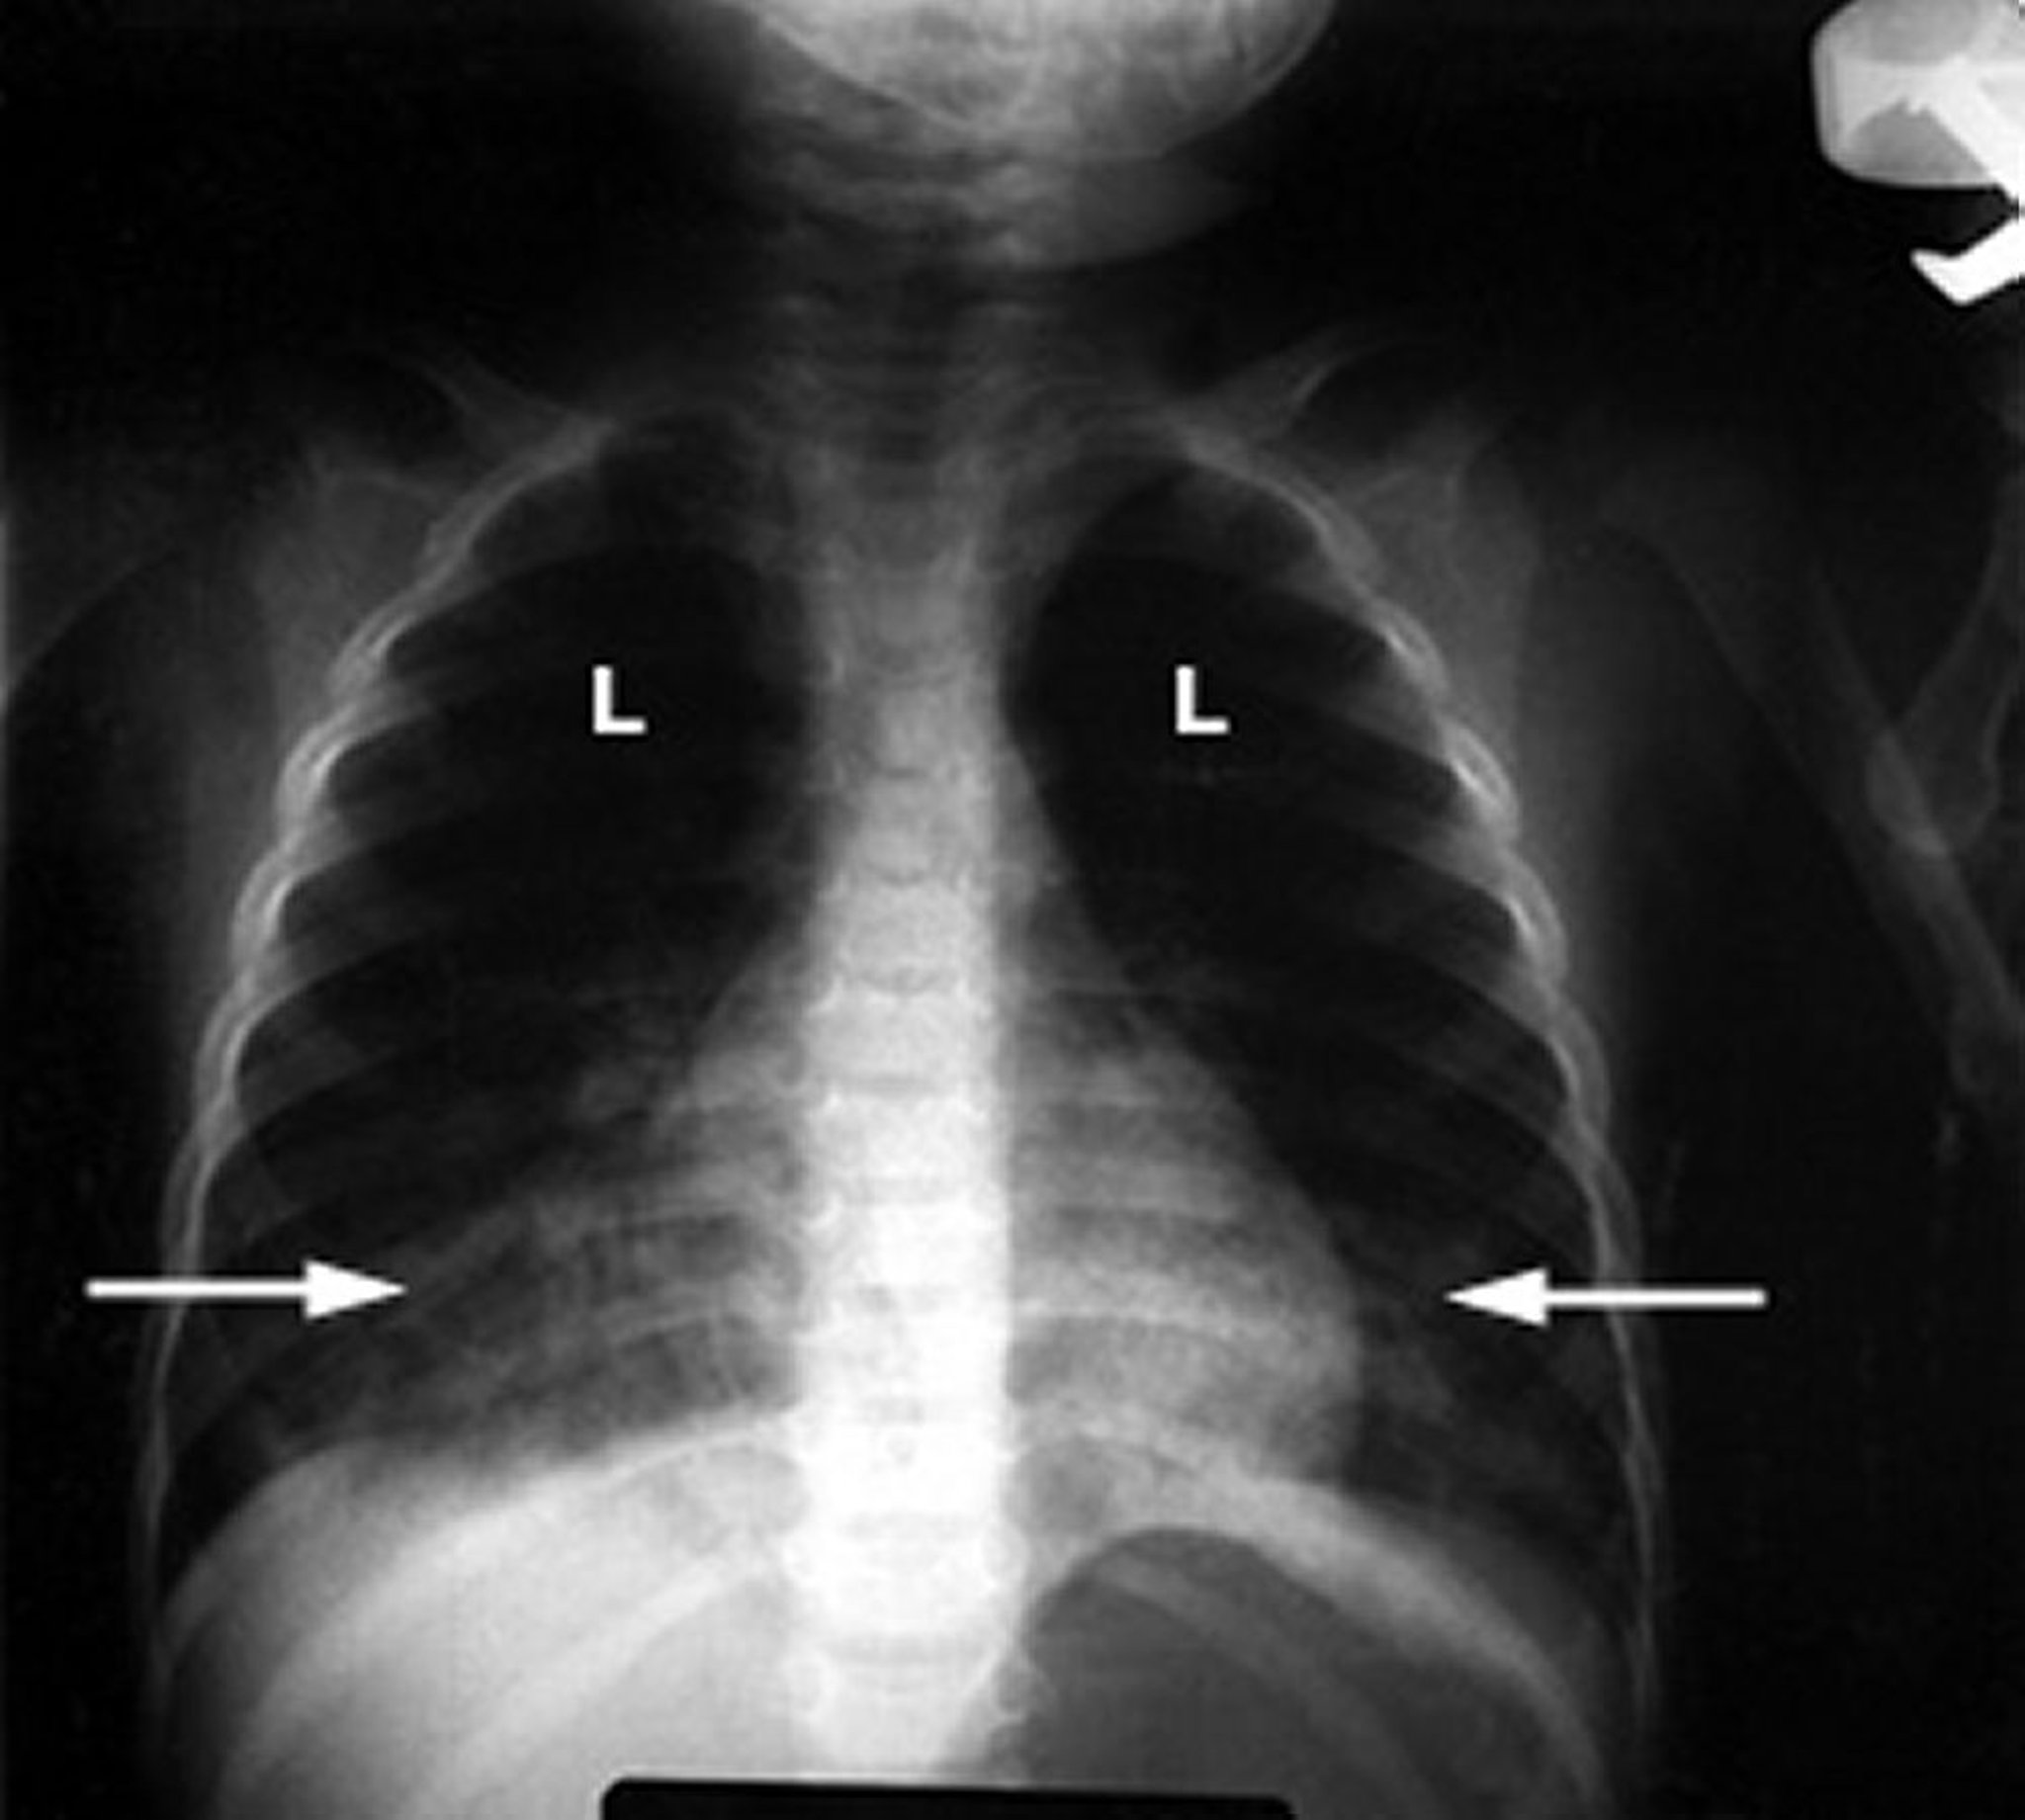

Polmonite chimica causata dall’inalazione di idrocarburi

Una radiografia toracica anomala nel bambino mostra infiltrati lanuginosi e bianchi (frecce) nei polmoni (L) che indicano infiammazione. Questo riscontro è tipico del danno polmonare dovuto all’avvelenamento da idrocarburi.

Per gentile concessione del Dott. G. Schmidt.